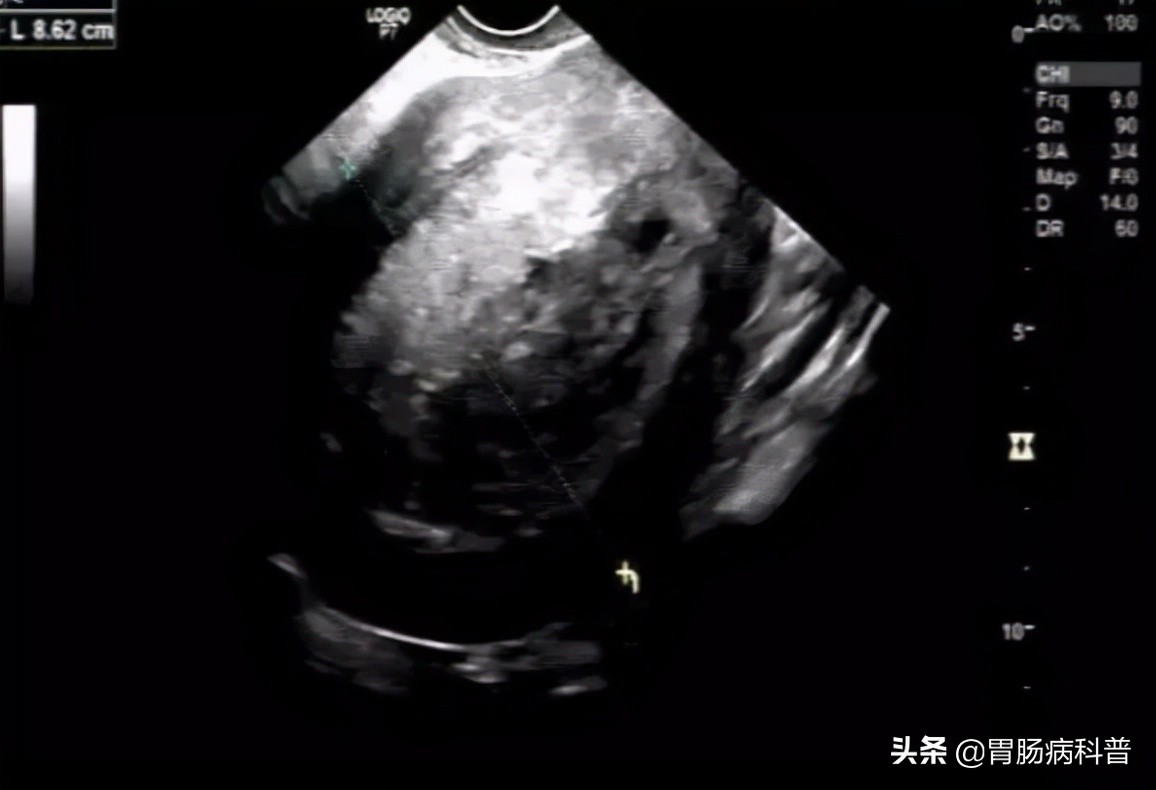

MRI和彩超回示:子宫内膜癌(?),待病理。